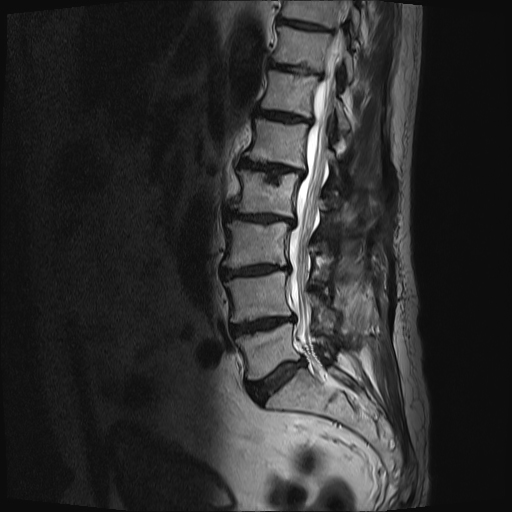

Die MRT-Bilder zeigen einen 78-jährigen Patienten mit Schwäche- und Taubheitsgefühlen in den Beinen, schon nach 20 Meter Gehstrecke.

Das erste Bild zeigt eine Einengung des Spinalkanals in 3 Höhen, das Zweite Bild zeigt den selben Patienten 6 Monate nach seiner OP.

Hier sieht man eine deutlich Entlastung der Nervenfasern. Im Gegensatz zum ersten Bild sind die Fasern nicht mehr gequetscht und zeigen um die Engstellen keine spiralförmige Aufwertung mehr.